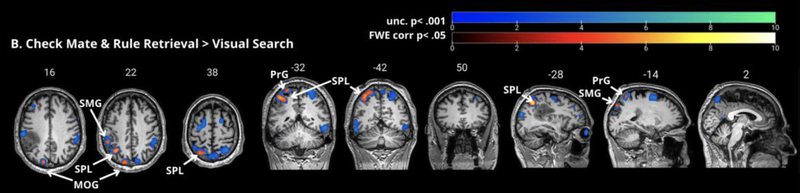

Let's be more specific and try to isolate some parts of the brain that are more uniquely involved in chess playing rather than broader cognitive and perceptual abilities. The researchers did that by using a different contrast that matches more low-level task demands across conditions. In the figure below, you can see the results of comparing just the Checkmate and Rule Retrieval conditions to the Visual Search task. Unlike the Resting contrast up above, this new contrast matches a bunch of simpler processes across both halves of the comparison: In both cases, you're seeing a chessboard. In both cases, you are probably naming and recognizing the pieces to perform accurately. In both cases, you have to come up with some motor response to meet the task demands. Because those processes are being carried out in both parts of the contrast, we wouldn't expect to see significant differences in activity in brain areas that support those tasks. What's left? Hopefully the brain areas that are specifically active when you're working out potential moves, including the possibility of a forced mate. If you take a look at the figure below, you can see that it's a lot less busy than the first one: Instead of that whole jumble of active regions, this is much pared down - if you consider just the regions that are still significant when implementing something called family-wise error correction (a technical step that is important but beyond our scope, I think), it's really just one spot! One spot up there in the left parietal lobe. One spot potentially close to the place where AB's surgeons need to resect a tumor. Now what?

Figure 7 (adapted from Cepero-Escribano et al., 2024) - A finer-grained comparison of chess-playing ability as assessed via move and checkmate evaluations compared to a visual search task on a chessboard. This contrast reveals significant activity in the left parietal cortex rather than a more distributed network of brain areas.